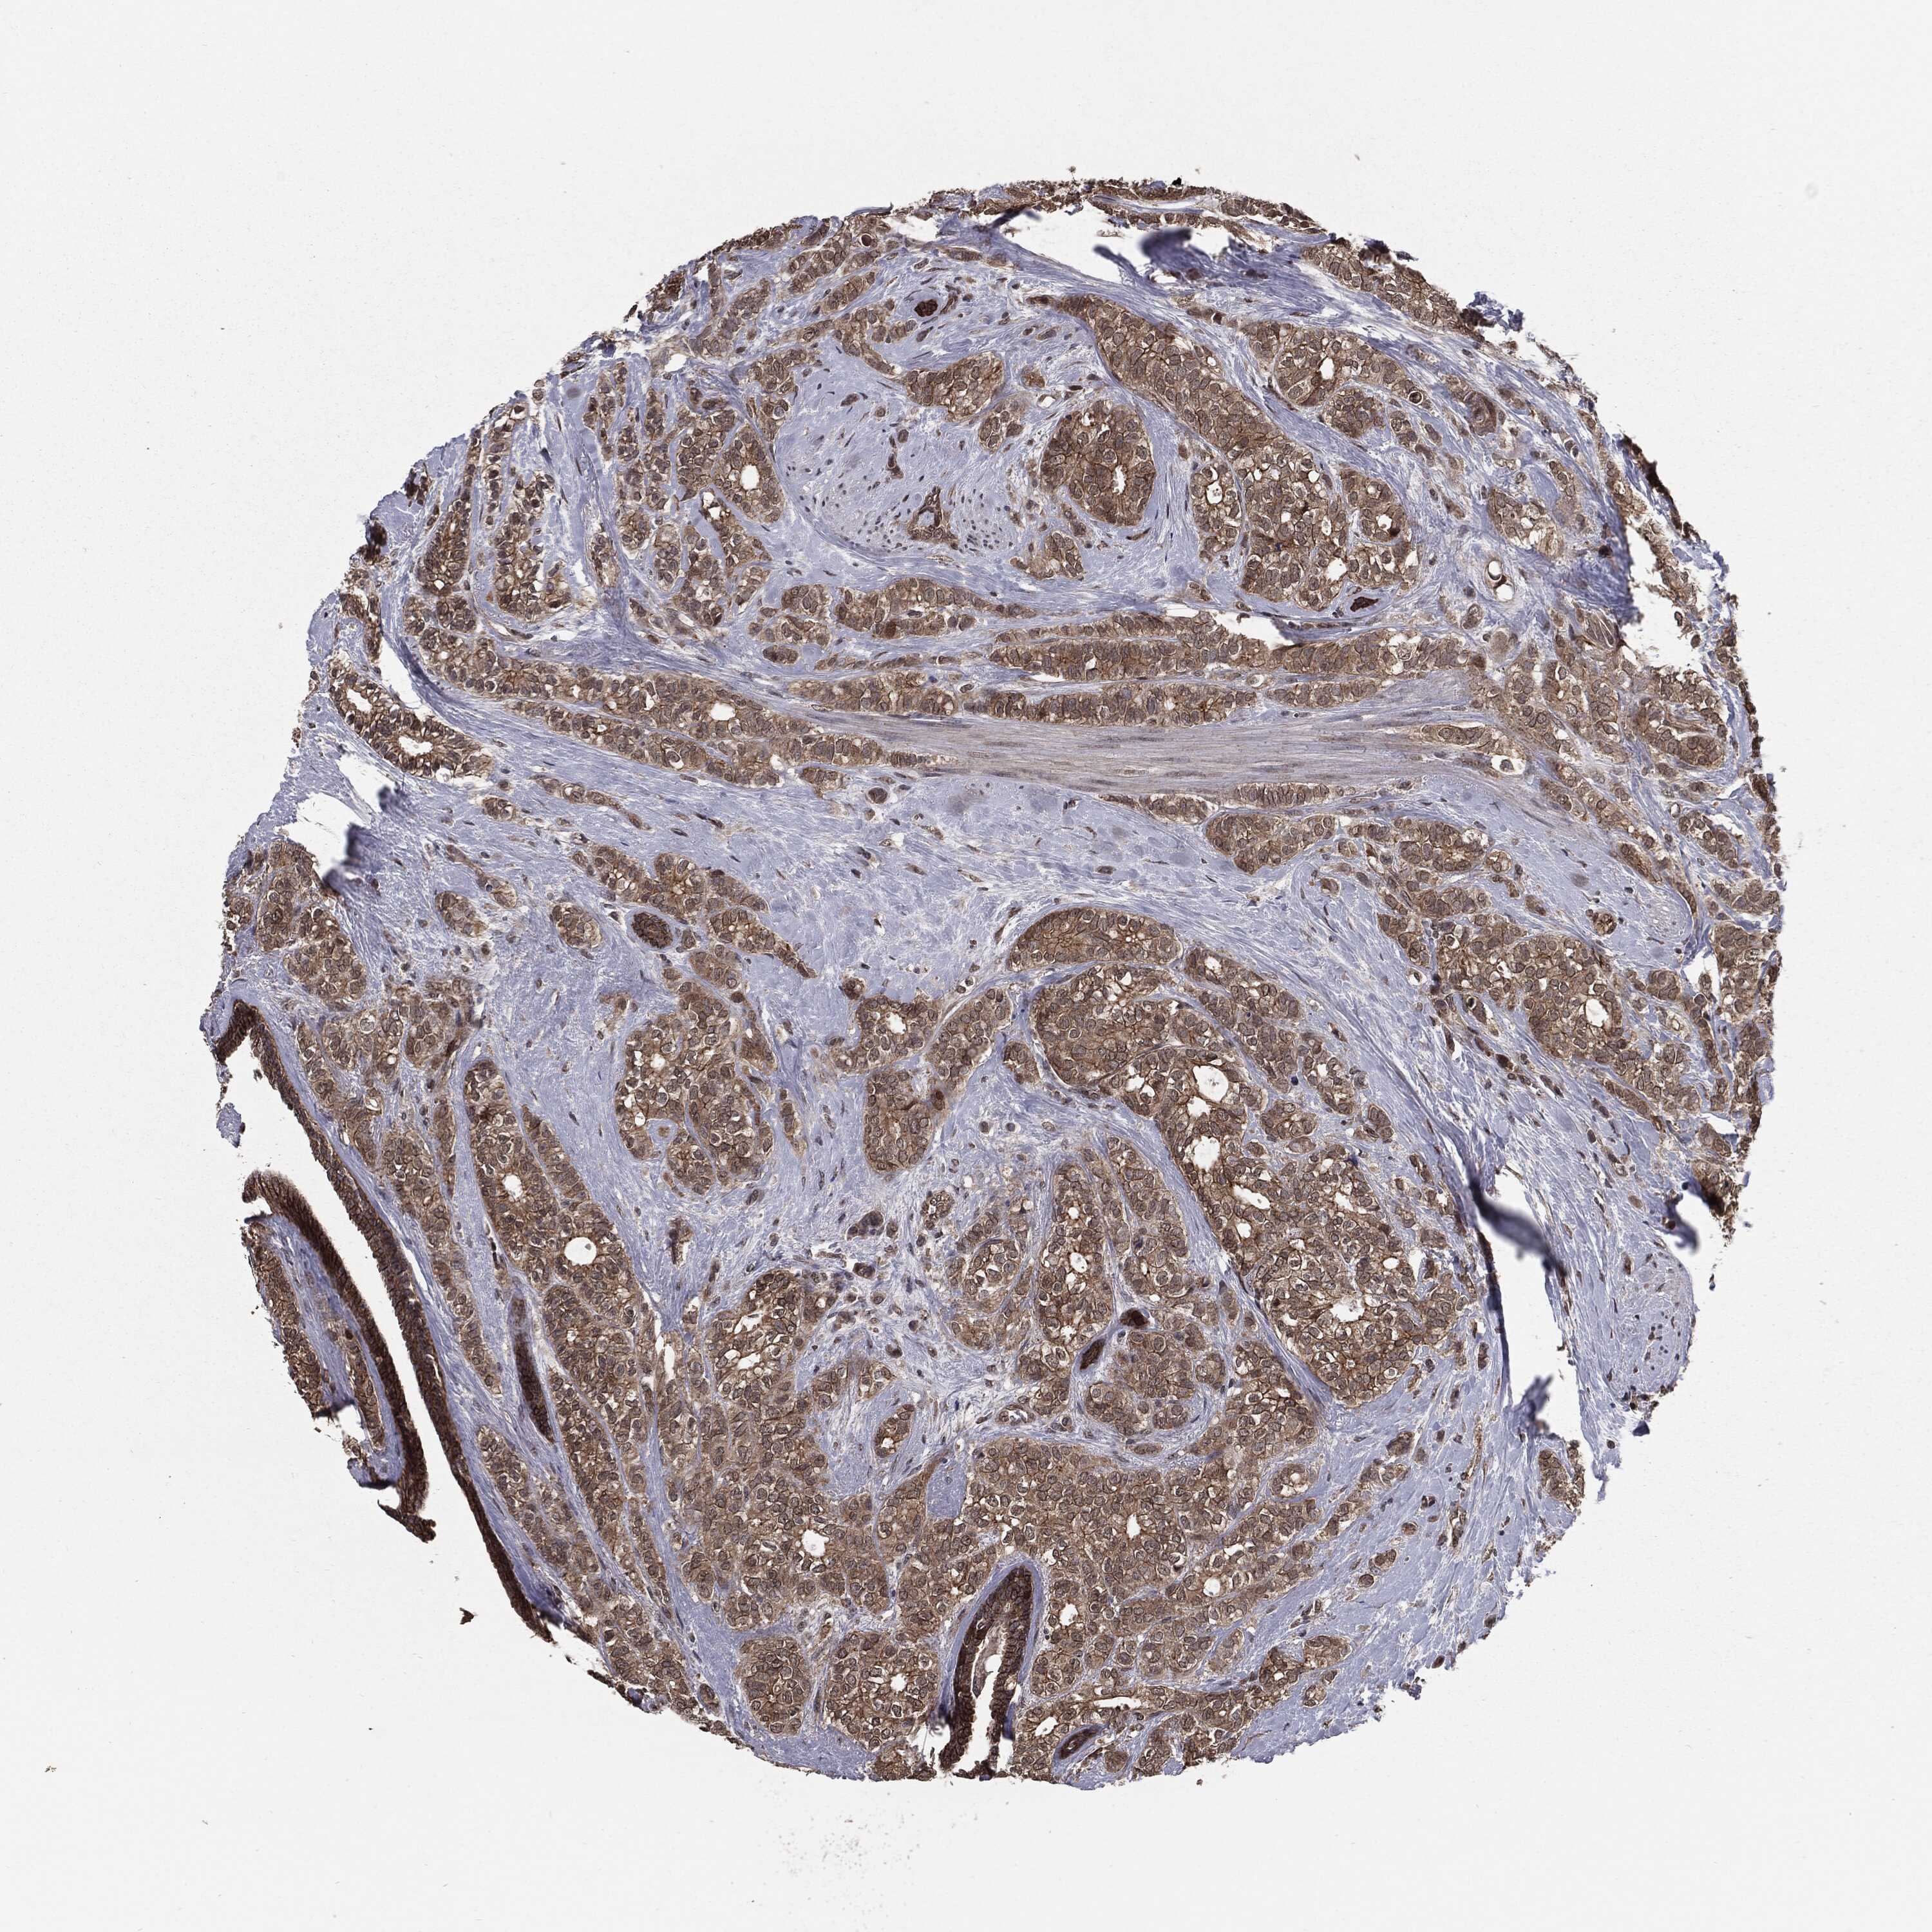

BRCA TCGA BRCA VALIDATION PROTEIN EXPRESSION

ANTIBODIES

AND

VALIDATION